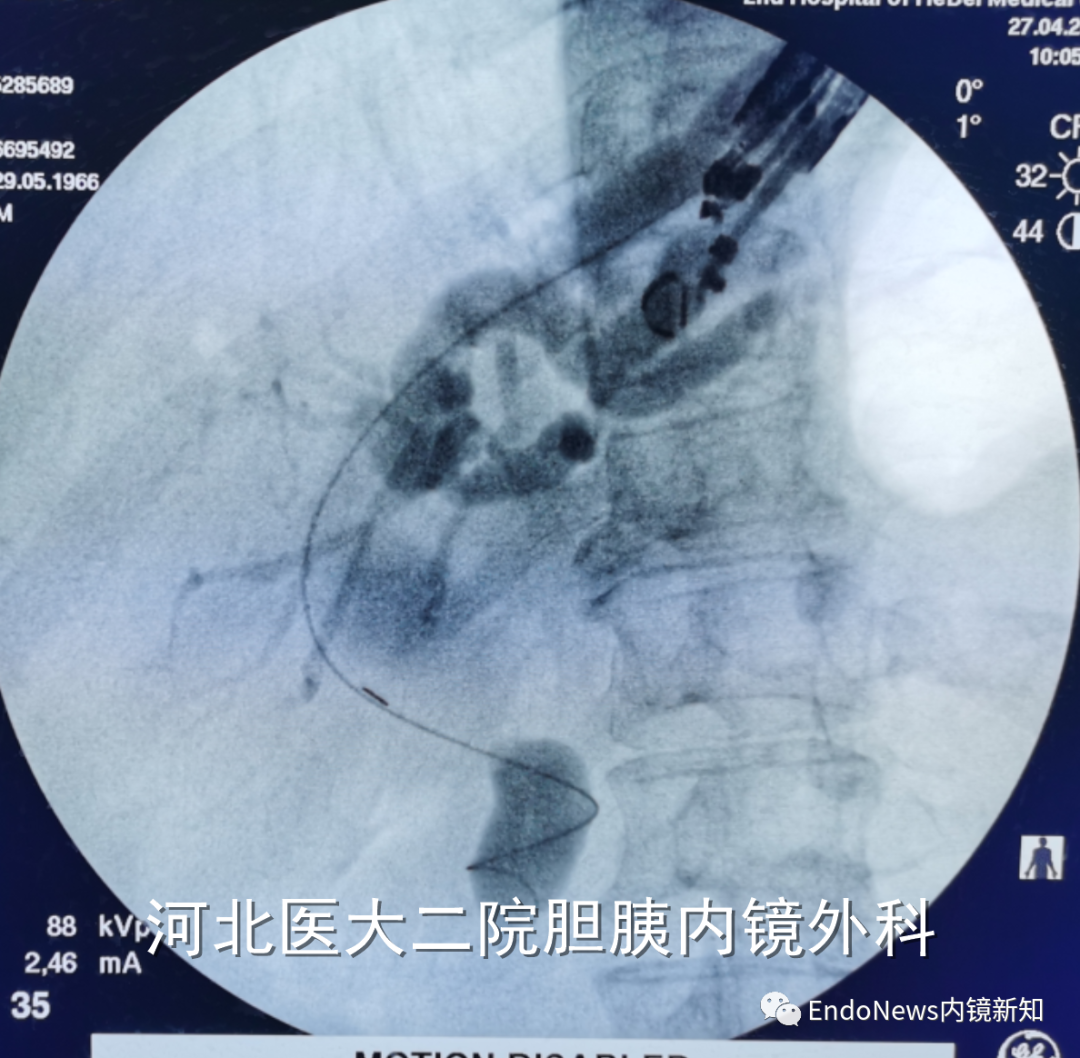

如下图所示,肝门胆管狭窄(Bismuth IV型),导丝进入肝右叶胆管后就可以置入支架引流肝右叶胆管:

取石网篮 为什么贵EUS-BD操作中的细节:导丝如何超选?_https://www.jmylbn.com_新闻资讯_第14张

在下面肝内胆管结石的病例所示,这是一个进肝右叶管之后顺行放置双猪尾支架,在二期手术时将窦道扩开,用字母镜液电碎石,再在右侧肝内胆管管进行取石的病例。